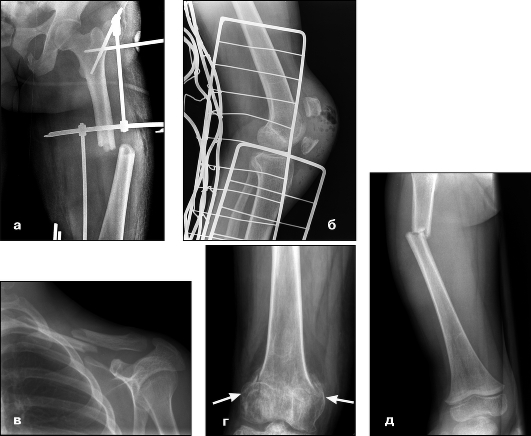

Как и при любой травме коленного сустава для постановки правильного диагноза выполняется рентгенография, на которой-то и можно увидеть перелом. Обычно рентгенографию выполняют в прямой и боковой проекциях, а для диагностики вертикальных переломов выполняют еще и осевую (аксиальную, или Merchant) проекцию.

Прямая (слева) и боковая (справа) проекции, на которых виден горизонтальный перелом надколенника со смещением отломков. Осевая проекция. Вертикальный перелом. Обратите внимание на возникшую в результате смещения ступеньку на скользящей поверхности надколенника.

Осевая проекция. Вертикальный перелом. Обратите внимание на возникшую в результате смещения ступеньку на скользящей поверхности надколенника.Иногда для более точного диагноза могут потребоваться компьютерная и/или магнитно-резонансная томография, но, в подавляющем большинстве случаев, достаточно рентгенографии.

К сожалению, рентгенография не всегда дает полную картину перелома, особенно перелом внутрисуставной. Для лучшего понимания перелома необходима дополнительная диагностика. Я всегда пользуюсь компьютерной томографией, которая помогает правильно спланировать операцию, подобрать правильные пластины, длину винтов.

Контроль стояния отломков на операционном столе это очередное условие успеха оперативного вмешательства. Благодаря современной мобильной рентгенследящей установки в нашей операционной качества выполнения операций значительно повысились.

Рентгеновские снимки коленной поверхности и профиля будут выполняться систематически. Осевой вид шаровых шарниров в сгибании при 30 ° часто бывает невозможным из-за боли. Эта минимальная рентгенографическая оценка позволяет подтвердить диагноз, указать тип перелома и искать связанные поражения в колене.

Рисунок 7: Перерыв в разрушении. Рисунок 8: Поперечный перелом; профильная рентгенография. Сканер имеет мало пользы; он может дать возможность указать суставное смещение. Трехмерные реконструкции интересны в случае сложных измельченных трещин. Артроскопии нет места для диагностики.

Для подтверждения диагноза необходимо выполнить рентгеновские снимки в двух проекциях, иногда требуется выполнение аксиальной проекции, особенно при вертикальных переломах. Обычно, перелом надколенника хорошо виден на рентгеновских снимках.